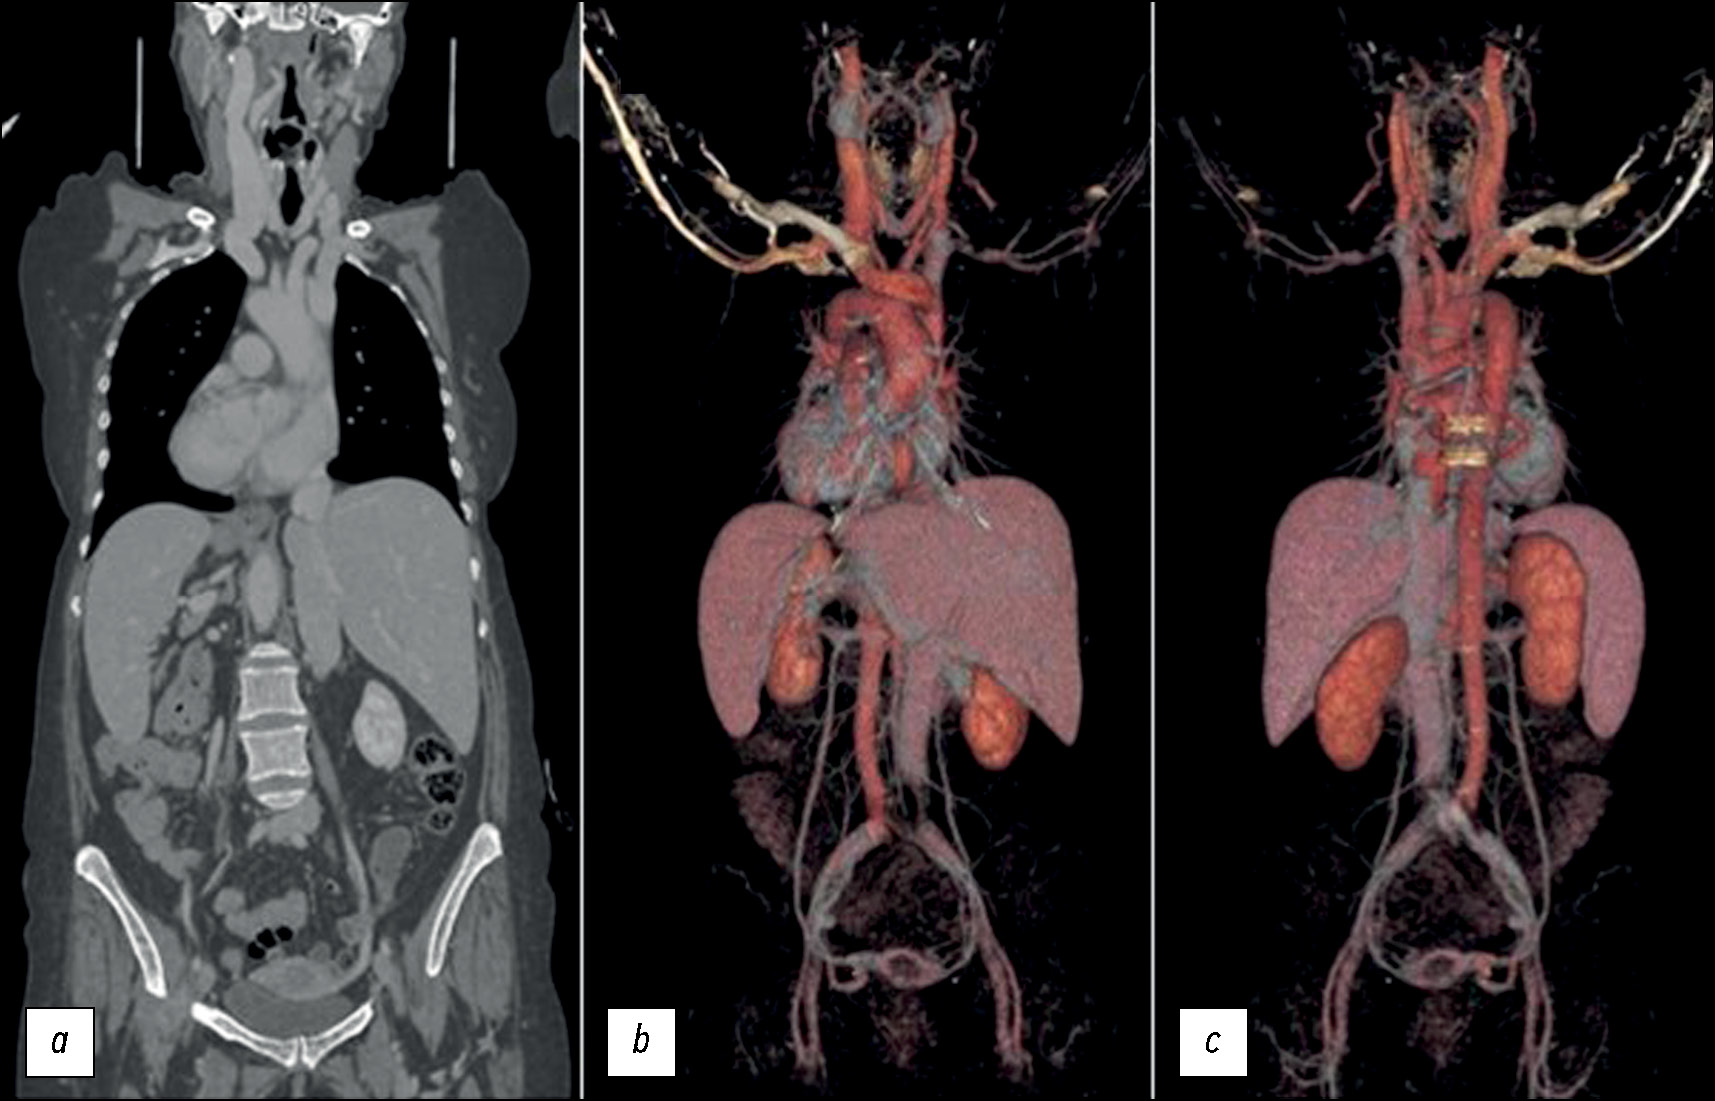

The contrasted CT confirmed the SIT: an asymptomatic situs viscerum inversus totalis (Fig. 4).

Fig. 4. The SIT is in a coronal plane of the CT (a) and two volume rendering (VR) VR images: (b) from the front and (c) behind.

In addition, the images from the high abdomen show a left-sided gallbladder with some micro-calculi, which could explain the clinical condition of recurrent flank pain on the left [1–7]. For the most part, this unsuspected discovery appeared completely innocuous for the patient’s health [9].